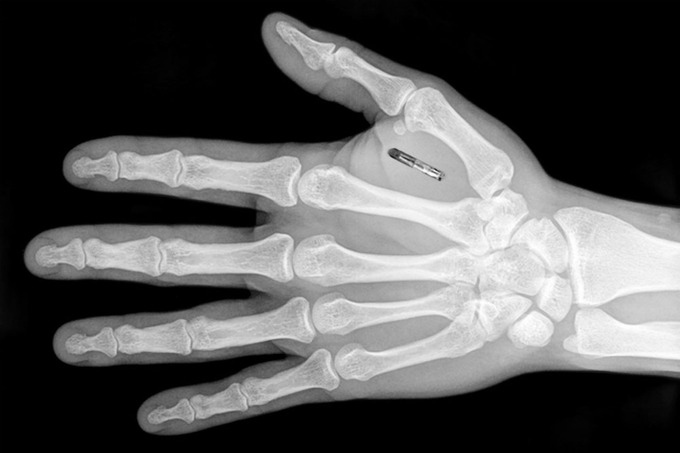

Чип размером с рисовое зерно имплантируется под кожу в области предплечья или между большим и указательным пальцами. Процедура по его установке безопасна, а спустя время его можно извлечь. Боль сопоставима с обычным уколом.

Фото: Next Nature